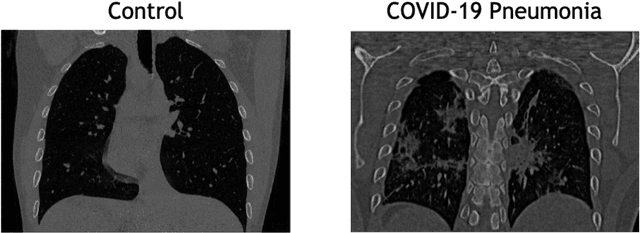

Abstract:The outbreak of the COVID-19 (Coronavirus disease 2019) pandemic has changed the world. According to the World Health Organization (WHO), there have been more than 100 million confirmed cases of COVID-19, including more than 2.4 million deaths. It is extremely important the early detection of the disease, and the use of medical imaging such as chest X-ray (CXR) and chest Computed Tomography (CCT) have proved to be an excellent solution. However, this process requires clinicians to do it within a manual and time-consuming task, which is not ideal when trying to speed up the diagnosis. In this work, we propose an ensemble classifier based on probabilistic Support Vector Machine (SVM) in order to identify pneumonia patterns while providing information about the reliability of the classification. Specifically, each CCT scan is divided into cubic patches and features contained in each one of them are extracted by applying kernel PCA. The use of base classifiers within an ensemble allows our system to identify the pneumonia patterns regardless of their size or location. Decisions of each individual patch are then combined into a global one according to the reliability of each individual classification: the lower the uncertainty, the higher the contribution. Performance is evaluated in a real scenario, yielding an accuracy of 97.86%. The large performance obtained and the simplicity of the system (use of deep learning in CCT images would result in a huge computational cost) evidence the applicability of our proposal in a real-world environment.